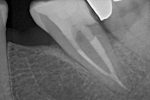

Revisionsbehandlung eines Unterkiefermolaren (37) vor geplanter Überkronung (Dr. Maik Göbbels) Download